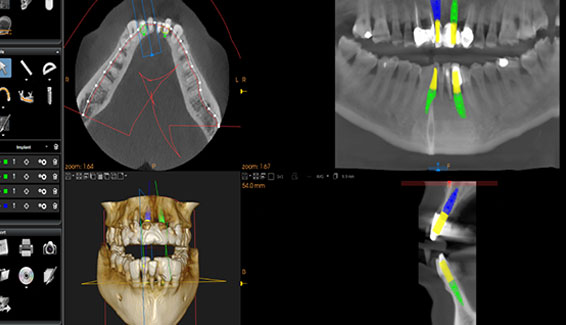

Dental Implants could be the best long-term solution to replace your missing teeth, so that eating the foods you love, speaking with confidence and smiling flawlessly will no longer be a distant dream. If you decide to get Dental Implants the first few steps would involve advanced planning with the help of clinical examination, 3D intra oral scans, high-definition photographs and CT scans. Once you are ready Dr Bopanna will use the surgical guide which was created using the scans to proceed with the treatment.

Sophisticated digital technology is used to carryout treatment planning to achieve excellent clinical outcomes. Apart from the high-definition photographs Carestream Software... Read More>>>